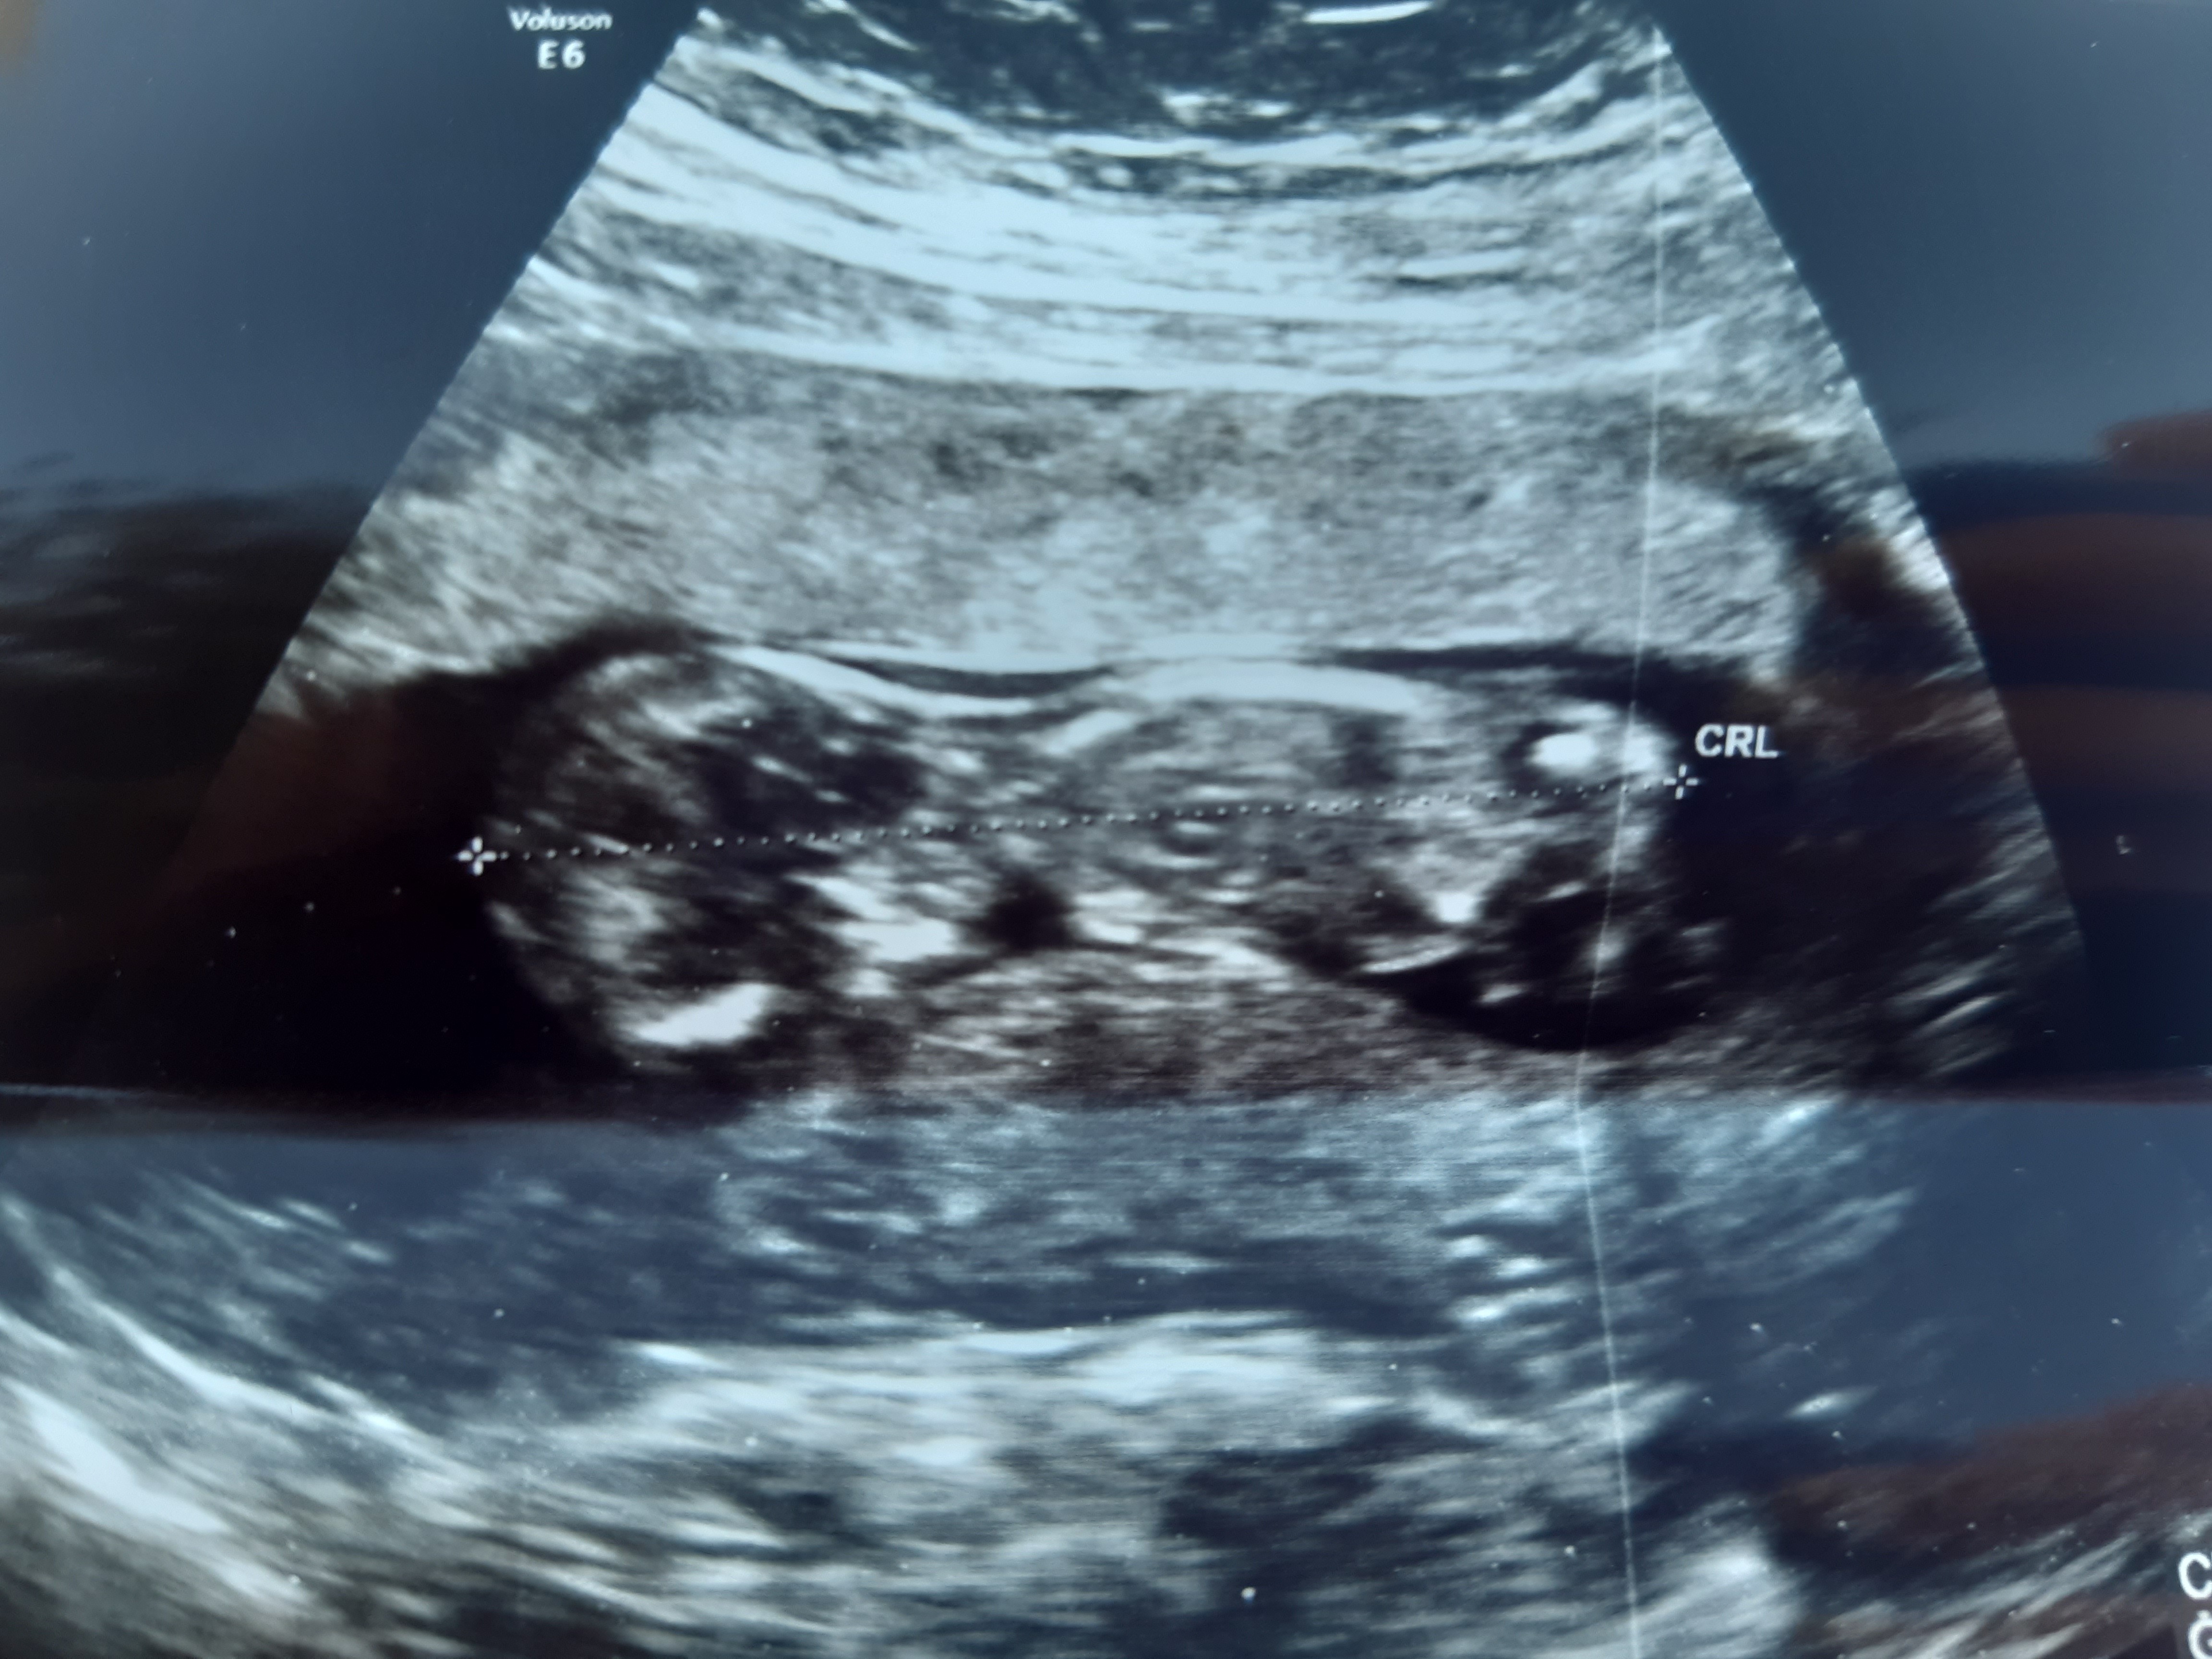

My Już Też po badaniu 😍 nasze maleństwo ma już 7cm A tak się wierci, że jak już poczuje ruchy, to będę stekac z boli jak moja mama że mną hahaha

Ogólnie, lekarz mówi, że z USG nie widzi przesłanek do Was genetycznych. Wszystko bardzo ładnie.

Powiedział, żeby się nie nastawić, bo nie ma 100% pewności, nie widać siurka 😂 więc będzie nasza Julcia 😍😍😍